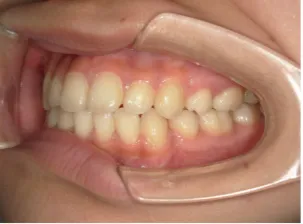

治療前①小2:8y1m 初診

治療中➁小3:9y8m QH、BH、前歯並び替え終了

治療後⑩高2:17y7m 抜歯治療終了

| カウンセリング・診断結果 | 前歯が受け口になっていているため、適正な成長へ誘導するために前歯の咬み合わせの改善が必要なことを説明し、診断を希望されたので精密検査へ進みました。 精密検査の結果、骨格的には受け口傾向、下顎前歯の突出、上下ともアーチが小さく凸凹(叢生)が認められ、機能的には低位舌と口唇閉鎖不全があり、口元は上下唇とも突出していますがコンケーブになってないことがわかりました。 |